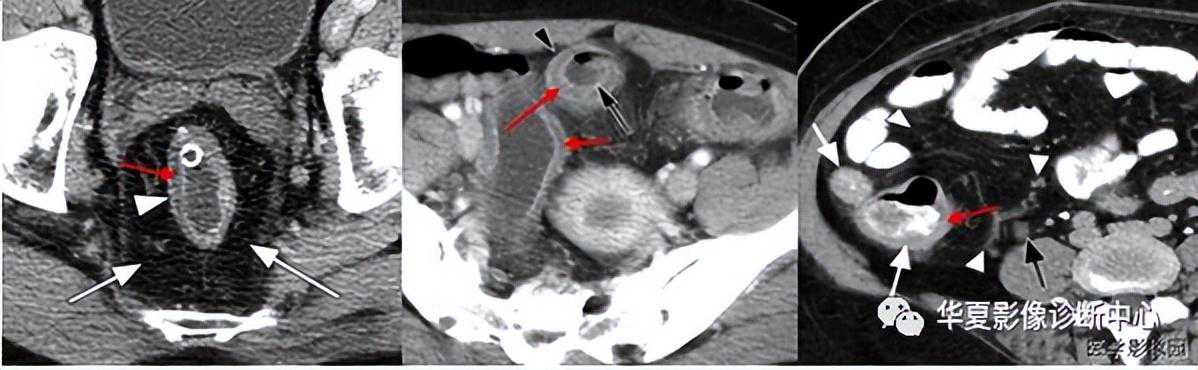

018:肾周晕征又名肾周晕轮征

【影像表现】CT上肾前筋膜增厚,肾前旁间隙渗出、积液,肾周间隙内脂肪密度被月晕状低密度影代替,低密度影CT值较高,可25Hu。

【征象解释】肾周晕征是急性坏死性胰腺炎(ANP)并发症的CT征象之一,急性坏死性胰腺炎疏松结缔组织炎由含蛋自酶的胰液外滋引起,常发生在胰尾,表现为肾前筋膜增厚。穿破肾筋膜累及肾周脂肪层,形成肾周晕征。

【讨论】急性胰腺炎病理学上分为2型:1)急性水肿型(间质型〕,较为常见,约占90%,胰腺呈弥漫性或局限性水肿,体积增大,间质水肿、充血和炎性细胞浸润。可有胰腺周围脂肪坏死,但无胰实质坏死改变。2)急性坏死型(出血型)。胰实质内腺泡和胰腺周围脂肪组织大片坏死,伴血管坏死出血,是本症的特点。腹腔内大量血性渗液,由于渗透液中含有大量胰脂酶,因而使网膜、腹膜及其他脂肪组织也大片坏死,此型病死率达50%。急性坏死性胰腺炎(ANP)可发生胰腺灶性或弥漫性坏死,并继发假性囊肿形成、感染、休克以及多器宫功能衰竭综合征等严重的并发症,病死率高。早期诊断ANP,早期评估胰腺坏死程度及严重度分级。并及时发现其并发症,是降低ANP病死率和提高生存率的关键。多排螺旋CT的出现及各种三维重建技术的应用,对ANP的评价优势更是日益突出,可反映胰腺及周围局部的情况,如胰腺实质有无坏死、胰周及腹膜后炎性扩散的范围、有无并发症等情况,为临床ANP诊断及治疗提供丰富信息。急性坏死性胰腺炎的CT诊断依据:

1)胰周积液CT值15hu,系单纯的胰周积液;如ct值较高,25Hu,是伴有脂肪坏死的指征;

2)胰腺内低密度影,CT值可降为0~22Hu;

3)增强CT示不强化区3cm或胰腺受累区30%,表现为点状、斑片状及大片状,如有出血时可见高密度影夹杂在低密度影中;

4)坏死的范围可分为弥漫性、局灶性和多发性。评估急性胰腺炎预后最常采用Balthazar分级标准:A级—胰腺正常;B级—胰腺肿大,弥漫性或局限性增大,密度不均或有小区域的积液,轮廓模糊,但不伴有胰周积液;C级—炎症蔓延至胰周。除胰腺实质异常外伴有胰周积液及胰周脂肪密度异常;D级—炎症扩散至胰外1个间隙,示境界不清的积液试和炎性肿块;E级炎症扩散至胰腺邻近2个以上的区域,示积液或积气。程燕等报道胰腺坏死.与腹膜后扩散范围的关系;根据Balthazar等的文献报道,胰腺坏死程度与腹膜后炎性扩展范围是急性胰腺炎的2个重要顶后指标。

在胰腺坏死50%的急性坏死性胰腺炎中,腹膜后炎性扩展范围分级达E级的占70%,统计发现急性坏死性胰腺炎胰腺坏死程度与胰周、腹膜后炎性扩展的范围大小之间存在着统计学意义上的关联性。其趋势是坏死程度越重,腹膜后炎性扩展范围分级越大,反之亦然。